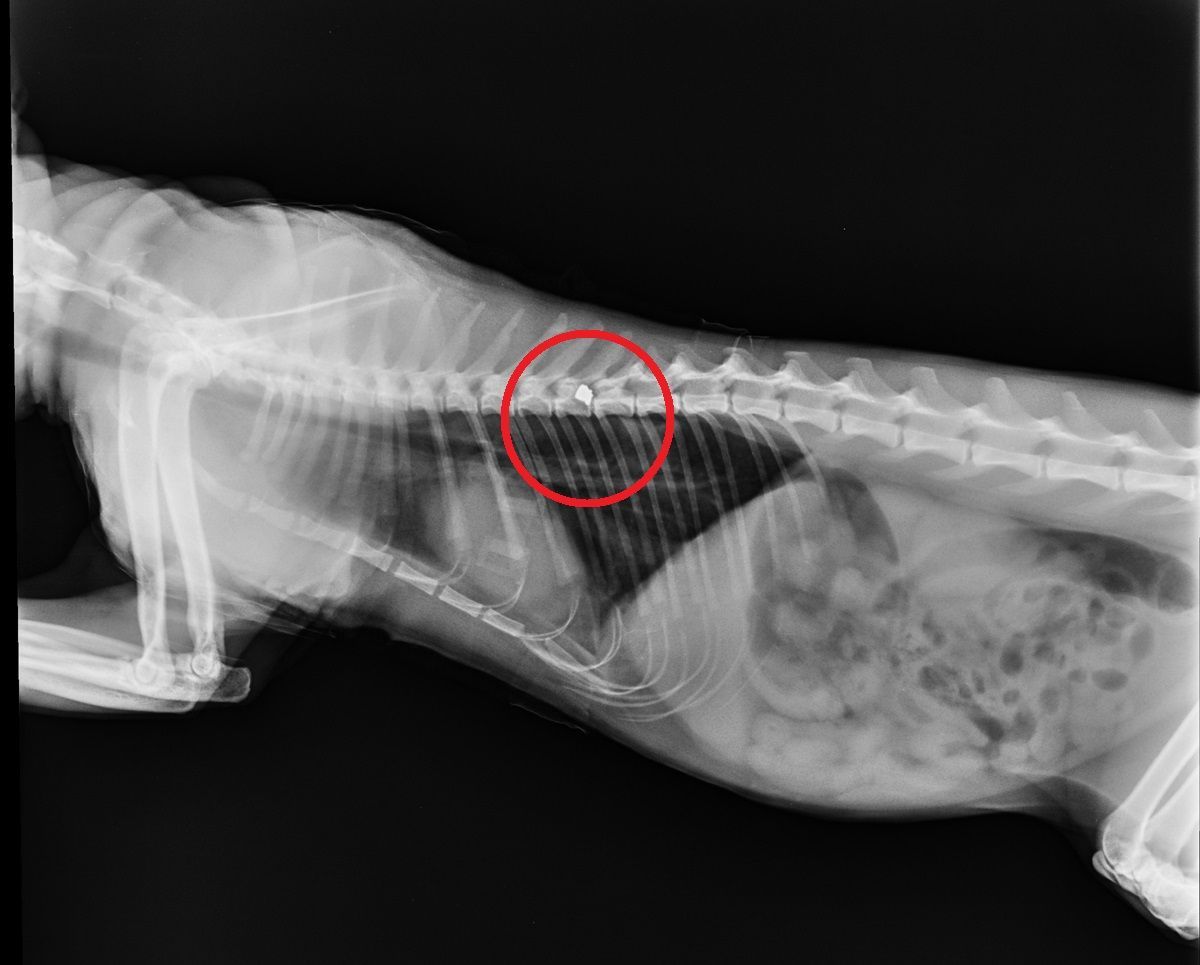

Τη μια από τις τέσσερις γάτες της βρήκε το απόγευμα της 15ης Αυγούστου η Έλσα Παπαδάκη τραυματισμένη στα πλευρά να μην μπορεί να αναπνεύσει – όπως αποδείχτηκε είχε πυροβοληθεί με αεροβόλο – στην Ποσειδωνία της Σύρου. Η γυναίκα μετέφερε στο ζώο στην Κτηνιατρική Κλινική Κυκλάδων στην Ερμούπολη και εκεί μετά από δύο ακτινογραφίες, που έβγαλε ο κτηνίατρος Μανώλης Βορρίσης εντοπίστηκαν τα δύο σκάγια στο κορμί του αρσενικού γάτου. Το ζώο υπέστη ρήξη της αρτηρίας και η κατάσταση του παραμένει σοβαρή εντούτοις γλύτωσε την αναπηρία αφού τα δύο σφαιρίδια δεν πέτυχαν την σπονδυλική του στήλη.

Η ακτινογραφία έδειξε τα σφαιρίδια του αεροβόλου στο κορμί του ζώου...

Η ακτινογραφία έδειξε τα σφαιρίδια του αεροβόλου στο κορμί του ζώου...